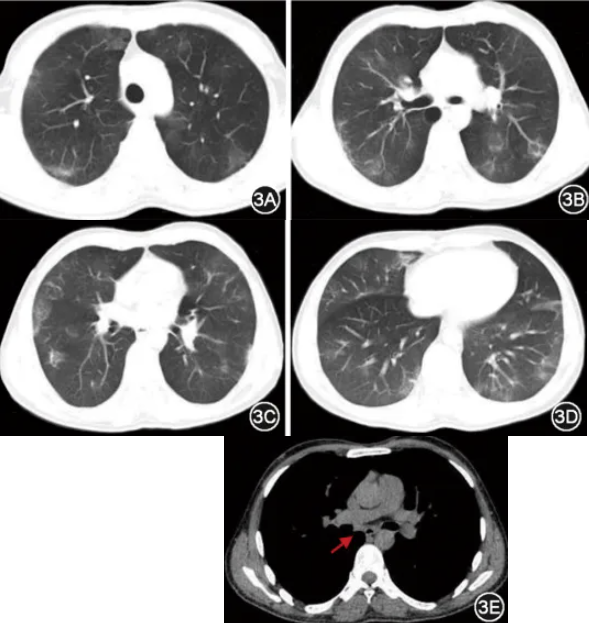

患者男性,37岁,藏族,牧民,主因“头痛10 d,发热、呼吸困难5 d”于2024年3月19日入院。患者10 d前出现头痛,以额部为主。5 d前出现发热,最高达39 ℃,伴呼吸困难,外院给予抗生素静脉滴注(具体不详),但呼吸困难加重。2 d前至急诊就诊,胸部CT提示双肺多发磨玻璃结节、渗出病变及实变,沿着支气管血管束分布(图1A~1D),7组淋巴结增大(图1E),头颅CT未见异常。动脉血气分析提示pH值为7.50,PaCO2为28 mmHg(1 mmHg=0.133 kPa),PaO2为39 mmHg(面罩吸氧8 L/min,拉萨,海拔3 650 m)。血常规提示白细胞计数、中性粒细胞计数增高(表1),淋巴细胞计数为0.45×109/L,血红蛋白172 g/L,血小板205×109/L。血生化提示丙氨酸转氨酶、天冬氨酸转氨酶及超敏C反应蛋白增高(表1)。血培养、鼻咽拭子呼吸道病原PCR、痰抗酸染色、结核分枝杆菌及利福平耐药检测(Xpert MTB/RIF)均阴性。急诊给予气管插管及机械通气,亚胺培南西司他汀钠(1 g,3次/d)及甲泼尼龙(40 mg,1次/d)静脉滴注,2 d后转入RICU住院治疗。既往体健,长居西藏浪卡子县(海拔4 450 m)。现吸烟15包年,偶尔饮酒。有食用生肉史。2024年1月在露天牧场为牦牛接生。

图1 2024年3月17日胸部CT可见双肺上叶类圆形磨玻璃结节(图1A,箭头),右肺上叶沿支气管血管束分布的实变(图1B,箭头),右肺中叶淡片状实变影(图1C,箭头),左肺下叶实变影(图1D,箭头),7组淋巴结增大,短径11.7 mm(图1E,箭头)

1940年春,贝纳柯克斯体首次被认为是肺炎的病因[6];Q热肺炎多见于中年男性,通常伴有发热、咳嗽、呼吸困难及头痛症状[7];胸部的体格检查通常无显著特征,最常见的是吸气末湿啰音,约5%的Q热肺炎患者有脾肿大[6]。实验室检查,与其他微生物引起的肺炎相比,白细胞计数一般正常或低,而C反应蛋白水平通常较高,显著高于其他肺炎[7, 8, 9]。Q热肺炎的影像学有一定特征性,对法国75例患者的胸部CT分析结果显示,最常见的影像学征象依次为肺泡实变(89%)、磨玻璃影(69%)、淋巴结肿大(40%),且病变以单侧分布为主(67%),而缺少肺炎链球菌的支气管增厚或(微)结节特征[10]。另有文献报道Q热1 261例,其中肺炎1 003例(79.5%),50%的肺炎患者住院,10例住进ICU[2]。本病患者以头痛起病,后出现发热和进行性呼吸困难。转氨酶升高至正常参考值的3倍,血象及炎性指标升高,本患者的影像学具有特征性,外周分布以类圆形磨玻璃结节为主,叶段分布的以多发实变和渗出为主,无支气管壁增厚的支气管炎的特征,突出病原以气溶胶形式吸入、均匀播散至肺脏而导致肺泡炎症的特点,这和常见CAP的病因以及其他吸入性肺炎的影像学不同,符合Q热肺炎的典型特征。